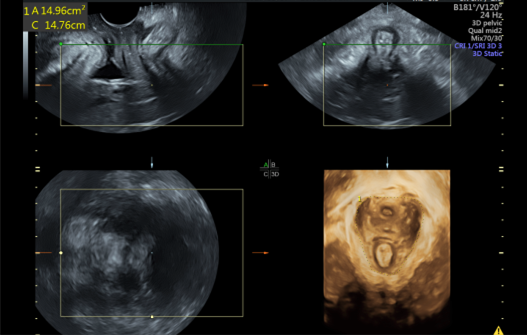

对于盆底疾病非常简单有效的一种检查手段就是盆底四维超声。可以动态观察盆腔脏器和盆底肌肉的形态结构和位置改变,对盆底的结构和功能有更全面的评估,还可以评价治疗后的疗效。